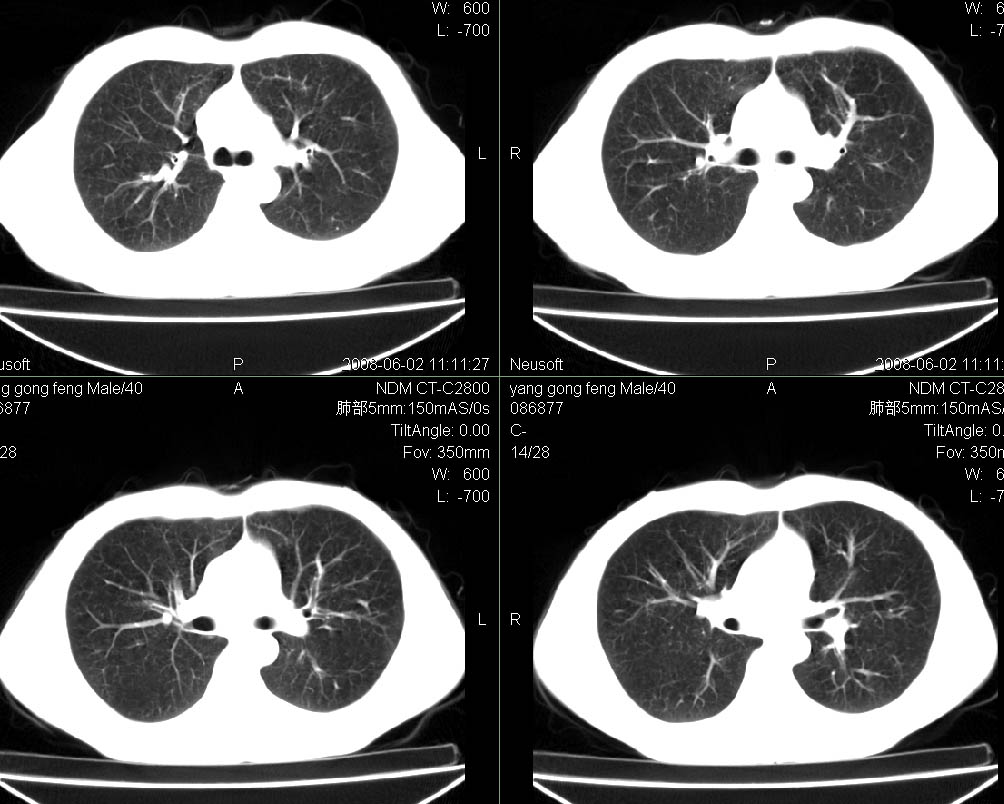

标题: CT15138:男,40,咳嗽胸痛. [打印本页]

标题: CT15138:男,40,咳嗽胸痛.

外院穿刺未见癌细泡,结核菌素实验阳性,未正规治疗2个月复查病灶及纵隔淋巴结增大

结合病史及临床表现考虑右侧中心型肺癌纵隔转移,

右肺中叶肺癌,纵隔淋巴结转移.

考虑   右肺中叶肺癌,纵隔淋巴结转移.建议穿刺活检。炎性假瘤待排

考虑右肺中叶周围型肺癌并纵隔淋巴结转移。